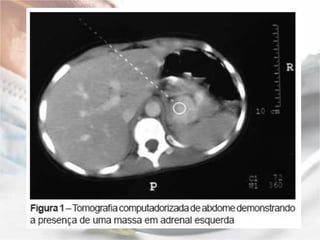

Localização:   A localização do feocromocitoma e feita com a utilização dos seguintes procedimentos radiológicos: tomografia computadorizada: com 85% a 95% de acuracia na localização de massas adrenais de ate 1 cm, não possibilitando a diferenciação entre feocromocitoma e metástases; ressonância nuclear magnética: que possui a capacidade de diferenciar feocromocitoma de adenoma ou carcinoma; mapeamento adrenal com I131 meta-iodobenzilguanidina (MIBG), de estrutura molecular semelhante a norepinefrina e que se concentra nas vesículas de estocagem de catecolaminas, possui 88% de sensibilidade, 100% de especificidade e 94% de acuracia na localização do feocromocitoma de ate 0,2 g de peso, de localização adrenal ou extra adrenal.